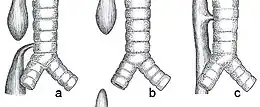

les différents types d'atrésie

- Type I

- Sans fistule. 7 à 10 %

- Aucun des culs de sac œsophagien n'est relié à la trachée. Les deux culs de sac sont souvent très éloignés l'un de l'autre.

- Type II

- Avec fistule. 1 %

- Fistule entre la trachée et le cul de sac supérieur de l'œsophage.

- Type III

- Avec fistule. 80 %

- Fistule entre la trachée et le cul de sac inférieur de l'œsophage. Les 2 culs de sac sont assez proches l'un de l'autre.

- Type IV

- Avec fistule : 4 %

- Fistule entre la carène de la trachée (ou la bronche droite) et le cul de sac inférieur de l'œsophage.

- Type V

- Avec fistule : 3 %

- Plusieurs fistules entre la trachée et le cul de sac supérieur de l'œsophage. Les 2 culs de sac sont le plus souvent très proches l'un de l'autre.